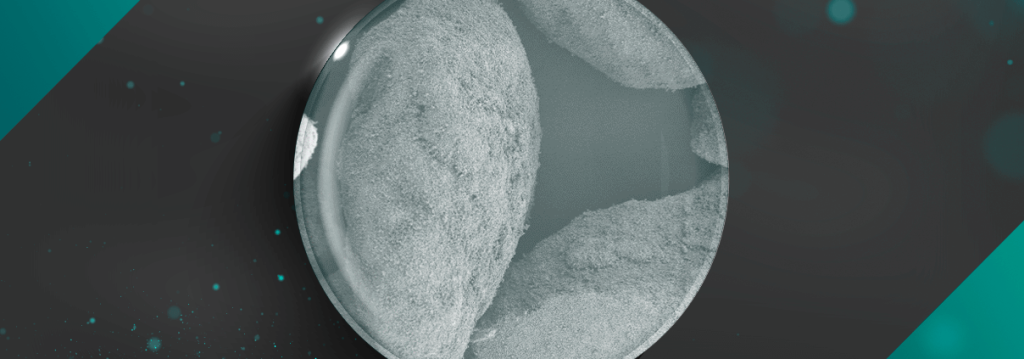

Nanosynt: Tecnologia que potencializa a formação óssea em tempo recorde

A Hidroxiapatita é reconhecida como o principal mineral presente em ossos e dentes. Além de sua função estrutural, favorece a adesão celular devido à capacidade superficial de adsorção para substâncias bioativas, incluindo proteínas adesivas celulares. Neste contexto, biomateriais à base de beta-tricálcio fosfato e Hidroxiapatita são muito utilizados em procedimentos de regeneração óssea em ortopedia […]